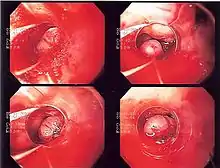

Endoscopic image of esophageal varices being ligated with rubber bands. The varix being ligated has a longitudinal red mark on it, termed the wale mark

A wale mark, red wale sign or wale sign is an endoscopic sign suggestive of recent hemorrhage, or propensity to bleed, seen in individuals with esophageal varices at the time of endoscopy. The mark has the appearance of a longitudinal red streak located on an esophageal varix. It derives its name from the visual similarity to patterns seen in the textile corduroy.[1]

Similar lesions that are suggestive of recent or impending bleeding from esophageal varices include the cherry-red spot, which is circular and red in colour. Bleeding risk of esophageal varices can be ascertained at the time of endoscopy by evaluating for the presence of these markers.[2]